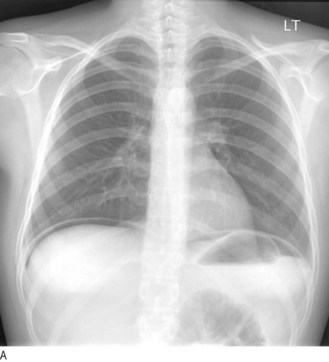

Fig. 8.29 Radiography in gastrointestinal disease.

(A) Air under the diaphragm on chest X-ray due to perforated duodenal ulcer. (B) Dilated small bowel due to acute intestinal obstruction. (C) Dilated large bowel due to toxic megacolon. (D) Dilated loop of large bowel due to sigmoid volvulus.